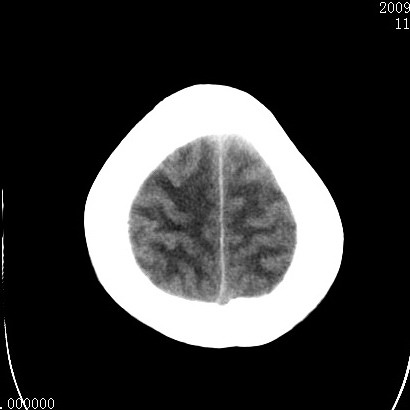

以下是引用余辉在2009-4-9 17:34:00的发言:[br]双侧脑白质对称性弥漫性密度减低,脑室脑沟裂池变小,双侧豆状核对称低密度,脑干对称性低密度,考虑1中毒性脑病2电解质异常(低钾钠等)3代谢异常及维缺乏等,进一步检查。